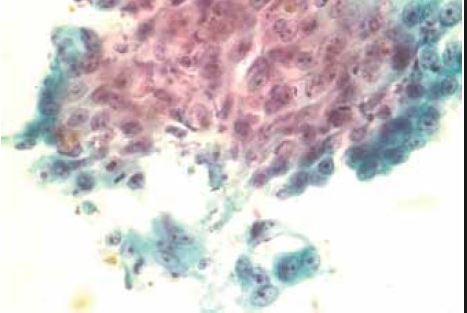

What is shown in this esophageal brushing cytology specimen?

A

Reactive changes/repair

Esophageal squamous mucosa with reactive changes, consisting of uniform cells with nucleomegaly in a predominantly cohesive flat sheet